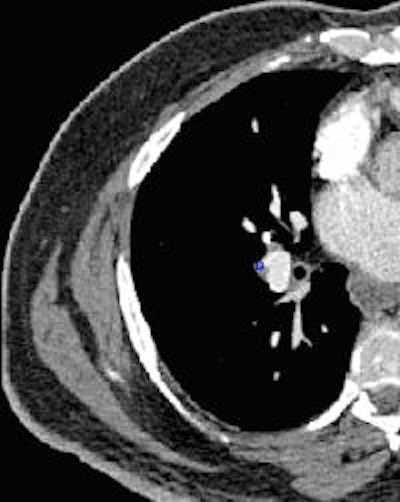

![]() |

| Segmental embolus indicated by blue square (right image) -- PE was missed by both inexperienced readers upon initial interpretation (left image) without CAD as a second reader. All images courtesy of Dr. Joseph Schoepf. |